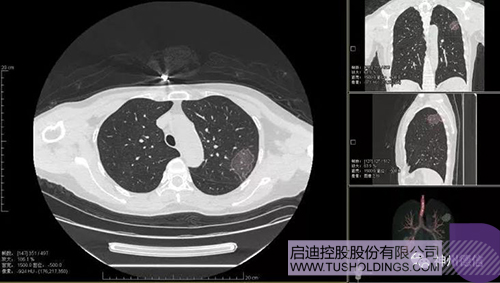

神州德信新冠肺炎检测及智能量化分析系统

开云(中国)战略投资企业神州德信作为国内领先的肺部影像人工智能企业,针对新型冠状病毒肺炎开发了智能检测及量化分析系统,并在陕西、重庆等地定点医院投入使用。该系统在疑似病例大规模快速筛查及精准诊断方面发挥了重要作用,特别是其具有的肺炎患者临床影像跟踪量化随访功能,为快速有效阻断疫情扩散提供了有力武器。